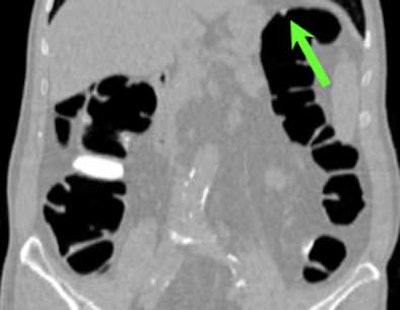

| Top to bottom: A 10-mm polyp in the splenic flexure can be seen in axial, sagittal, coronal, and 3D views. All images courtesy of Dr. Riccardo Iannaccone, University of Rome "La Sapienza." |